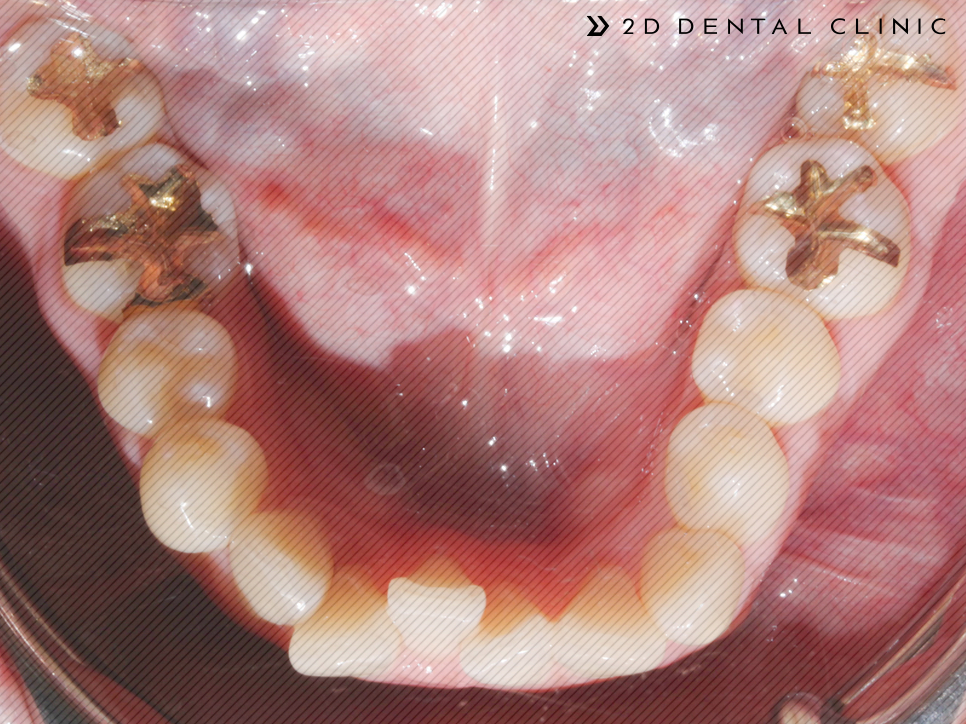

다시 전후 케이스 리뷰로 돌아와서! 본 환자분은 심한 크라우딩 상태에 상악의 제1 대구치(첫 번째 큰 어금니)가 없으신 상태셨답니다.

전체 교정인 클리피씨로 진행되었고 상악의 양쪽의 제1소구치를 발치하였습니다. 제2 대구치는 미니스크류로 당겨드렸고요.

전체적인 크라우딩의 개선

교정기간은 1년 반이 소요되셨답니다~ 전체적인 크라우딩이 개선되고 치아 배열이 고르게 개선되었습니다.